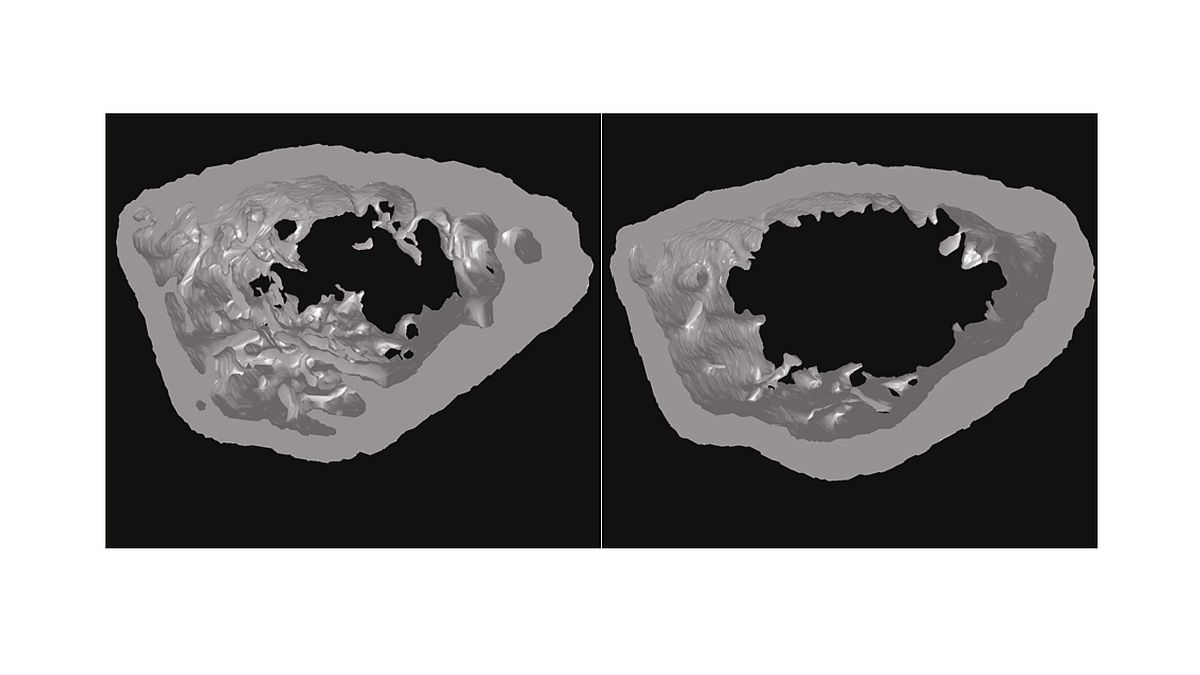

Another side-effect of the seven-year-long research: In some cases, the loss of menin in the osteoclasts of mice led to the formation of a tumour in the lower jaw. Experts of the Bone Tumour Reference Centre in Basel, a cooperation partner of the CME, pointed out the similarity with the ossification syndrome found in humans. This little researched tumour disease leads to heavy cell growth in the lower jaw. At present, this very rare, benign tumour can only be treated with invasive and disfiguring surgeries. Until now, little was known about the triggering factors of this tumour disease. In a mouse model, the researchers in Ulm have now discovered that menin controls the cell growth inhibitor p21 - and thus suppresses the growth of tumours. When menin is absent, p21 reduces its activity and certain cells start to grow increasingly.

Bone tissue is the result of a complex remodelling process (osteogenesis). This requires the perfect coordination of bone formation and resorption. In consequence, cells that break down bone (osteoclasts) are equally important as bone-forming cells (osteoblasts).

Osteocytes, on the other hand, are the bone cells found in the mineralised matrix of bone tissue. They arise from the differentiation of osteoblasts during bone formation.